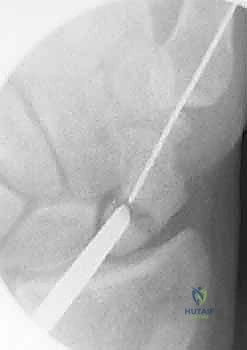

هذه هي التقنية المتقدمة التي يبرع فيها الأستاذ الدكتور محمد هطيف في صنعاء. بدلاً من فتح الرسغ، يتم إجراء العملية بأكملها من خلال شقوق دقيقة لا تتجاوز 2-3 مليمترات، تحت إرشاد جهاز الأشعة المرئية (Fluoroscopy) وبمساعدة المنظار المفصلي الدقيق.

العملية الجراحية بتقنية التدخل المحدود ليست مجرد "إدخال مسمار"، بل هي عمل فني وهندسي دقيق يتطلب مهارة جراحية فائقة، تخطيطاً مسبقاً، وتنسيقاً مثالياً بين يدي الجراح والصور الإشعاعية. يتبع الأستاذ الدكتور محمد هطيف بروتوكولاً صارماً لضمان أعلى معدلات النجاح.